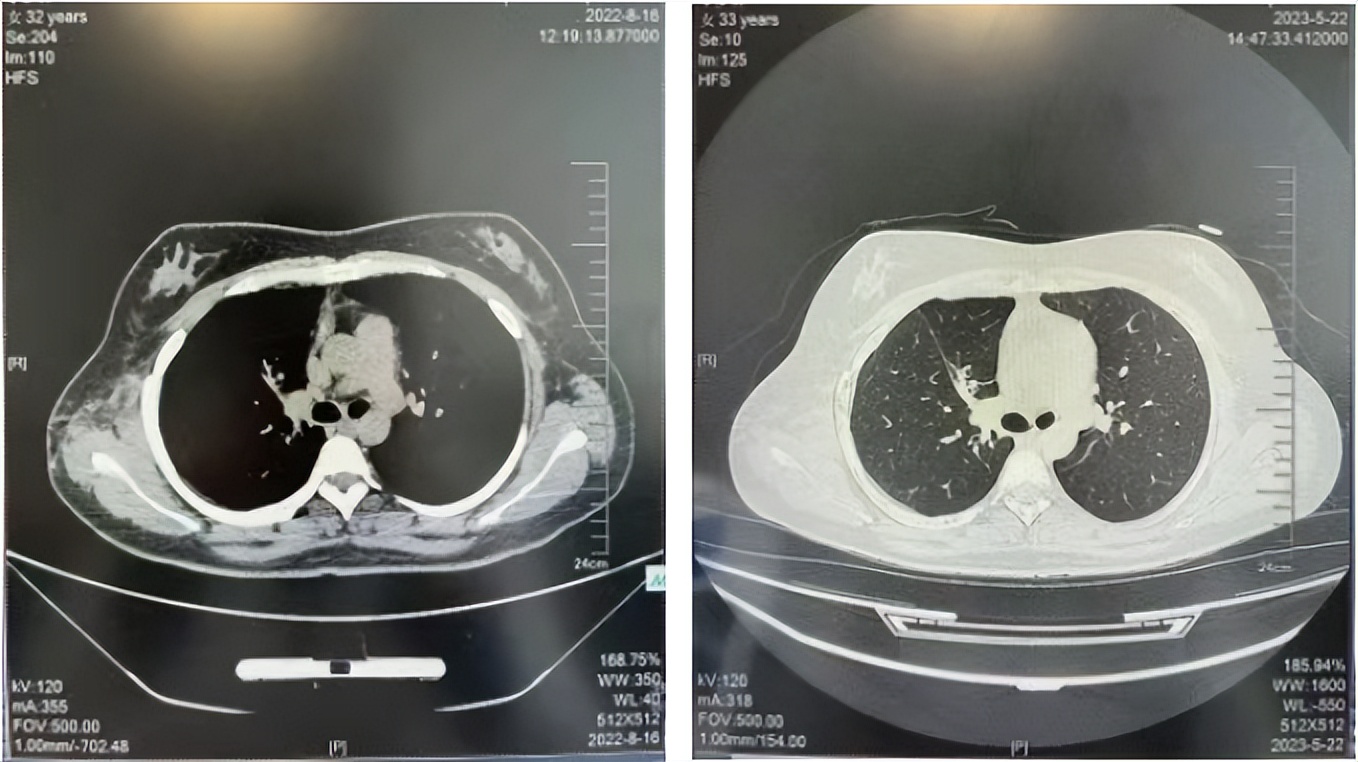

2016年1月复查CT提示支气管截断可见新发小结节,一线治疗采用培美曲塞+DDP方案化疗4周期(培美曲塞3.36,DDP 480mg)。化疗后复查胸部CT:右肺见不规则结节样影,最大层面大小约19mm*8mm,较前比较明显增大,疗效评估PD。2017.3-2017.4予单药多西他赛化疗3周期,疗效评估SD。2018年5月末复查CT提示结节较前增大,评效为PD,2018年6-10月予多西他赛+CBP化疗4周期,疗效评估SD。2022年5月患者出现活动后气短,复查胸部CT示右肺膨胀不良;右侧胸腔积液增多。胸腔积液包埋病理示符合肺腺癌细胞。行NGS基因检测:EML4:exon13-ALK:exon20融合。PD-L1(克隆号22C3)TPS<1%。

临床诊断:右肺上叶恶性肿瘤rT0N0M1a IVA期(第9版分期);恶性胸腔积液。

诊疗经过:2022年5月始口服克唑替尼3个月,出现肝功能异常(DILI 2级伴临床症状),改用恩沙替尼靶向治疗至今,目前评效为维持PR。恩沙替尼应用期间出现轻度肝功能异常(DILI 1级),对症处理后好转。截止目前PFS 33个月。

2018.07

2022.05

2022.08

2023.05

2024.12